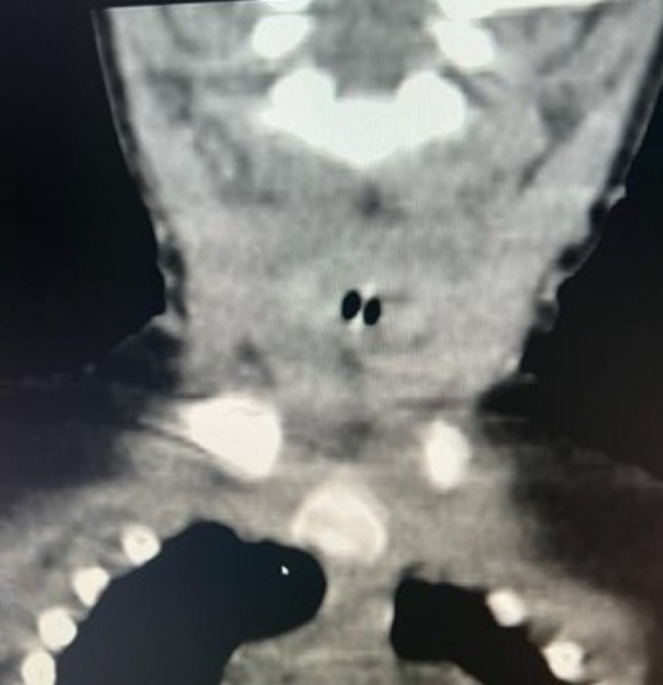

吸入异物在儿童中很常见,可能会危及生命。可以发现不同类型的异物,但喉部定位是罕见的。我们在此报告一例8个月大的男婴谁提出呼吸窘迫,发音困难,和喘。入院时,患儿表现出严重的喉部呼吸困难。颈椎CT扫描显示喉部有一不透射线的异物。内窥镜提取显示声门下有一阻生鱼椎体。位于下气道喉部的异物是罕见的,发现鱼椎骨是例外。

Inhalation of foreign bodies, a common occurrence in children, can be life-threatening. Different types of foreign bodies can be found, but laryngeal localization is rare. We here report the case of an 8-month-old male infant who presented with respiratory distress, dysphonia, and stridor. On admission, the child exhibited severe laryngeal dyspnea. Cervical CT scan revealed a radiopaque foreign body in the larynx. Endoscopic extraction revealed an impacted fish vertebra in the subglottis. Foreign bodies located in the laryngeal area of the lower airways are rare, and the discovery of a fish vertebra is exceptional.